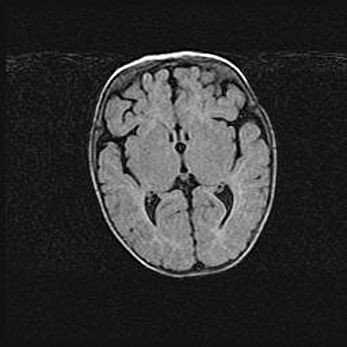

Церебральная ишемия II.

Возраст: 5 дней

Вес: 3400 г

Пол: женский

Окружность головы: 35 см

Срок гестации: 39 недель

Церебральная ишемия – это заболевание, характеризующееся недостаточностью (гипоксией) либо полным прекращением (аноксией) снабжения мозга кислородом по причине закупорки одного или нескольких сосудов. Это приводит к  что метаболическим расстройствам различной степени тяжести в тканях головного мозга, развитию коагуляционных некрозов и гибели нейронов.